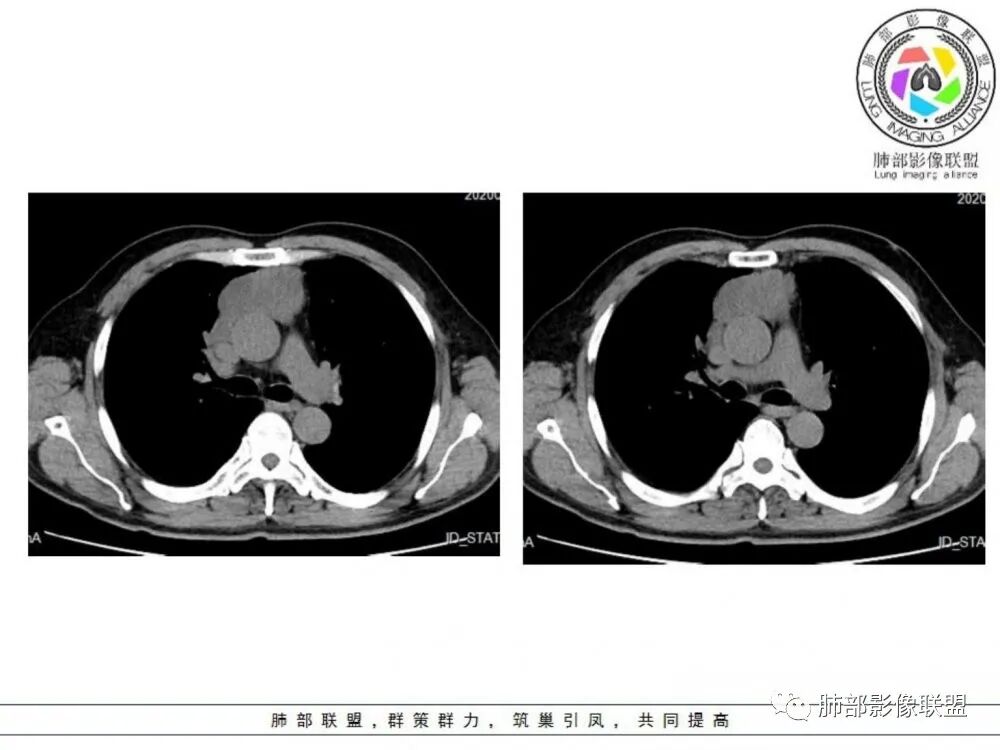

男性患者,65岁,前胸后背疼痛一个月。影像学前上纵隔分叶状的软组织肿块,肿块形态怪异,偏软,位于大血管间隙前,并有向血管后间隙发展的趋势,平扫CT值为40左右,增强扫描中心部未见强化,周围轻度的强化,约为50左右。前上纵隔的疾病谱包抬胸廓内甲状腺肿、胸腺瘤/癌、畸胎瘤、淋巴瘤。少见的心包囊肿或支气管囊肿。根据肿块的形态及强化特点,首先还是排除了胸内甲状腺肿及胸腺来源的肿物,这类的肿物强化比较明显。畸胎瘤成分比较复杂,具有软组织钙化或者脂肪类的组织,这个肿物虽然在平扫的时候好像有斑点状的钙化灶,但是总体成分还是比较单一,所以还是排除畸胎瘤的诊断。所以这样的情况是考虑:淋巴类的肿瘤,注意排除心包的囊肿或支气管来源的囊肿。

老年男性患者,前膈软组织肿块,边缘轮廓不光整,边界似乎尚清晰,内见小点状钙化灶,平扫密度欠均匀,增强后轻度强化表现,边缘有些斑片状的高强化区。综合考虑胸腺瘤或胸腺鳞癌,神经内分泌癌强化弱了一些。患者年龄较大,生殖细胞肿瘤不考虑,淋巴瘤血管包绕不够,可能性不大

老年人前纵隔占位的占位应该就是胸腺瘤、胸腺癌与淋巴瘤的鉴别吧,病灶本身膨隆生长,内坏死边界不清,纵隔未见明显肿大淋巴结,相邻内乳淋巴结不大,周围血管见分界不清,考虑胸腺鳞癌。

前纵隔胸腺区分叶状软组织肿块影,轻度不均匀强化,中心可见坏死,边缘不清,病灶与邻近心包见条索影,上腔静脉受侵,上纵隔多发小淋巴结,考虑胸腺鳞癌可能。

老年男性,前纵隔肿块,形态不规则,右侧内乳动脉增粗,与血管脂肪间隙模糊消失,定性恶性,周围多发小淋巴结,有斑点状钙化灶,增强中心低密度区无强化,边缘强化为主,首先考虑胸腺鳞癌,鉴别胸腺瘤。

中老年男性,前纵隔占位,基本居中,向两侧生长;边缘膨隆分叶,部分边界不清,增强不均匀轻中度强化,坏死区边界不清;周围多发增大淋巴结,考虑恶性。主要在胸腺癌、胸腺瘤、淋巴瘤之间鉴别。病灶偏软,有钻缝样生长,这些征象偏向于淋巴瘤。但此例老年患者,病灶内有点状钙化,缺乏结节堆砌感,倾向胸腺癌诊断。